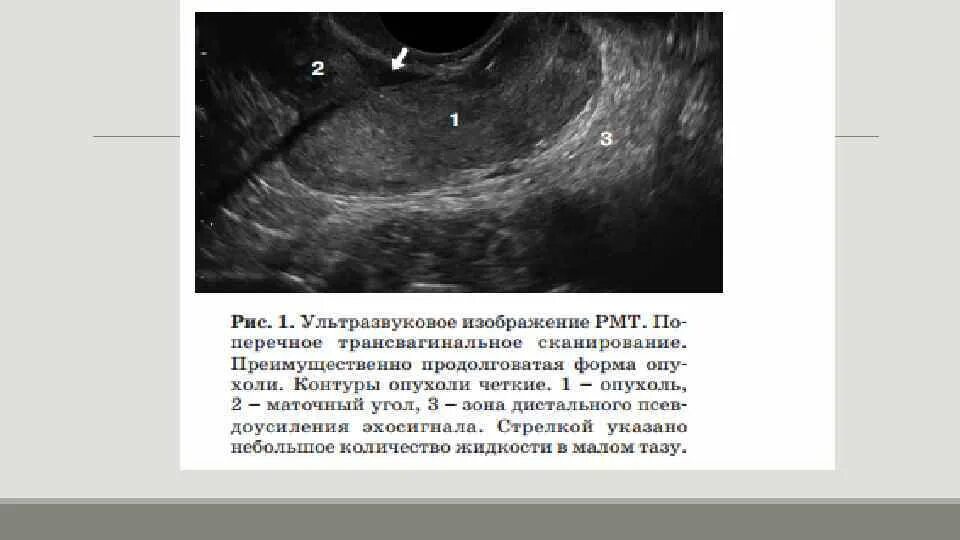

Содержимое в маточной трубе